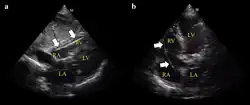

Exemplo de ECG do dispositivo a) flutuando livremente no VD b) em contato com a parede do VD

É possível colocar o eletrodo no seio coronário, normal (esquerdo) dilatado (direito). Tal colocação é aceitável.